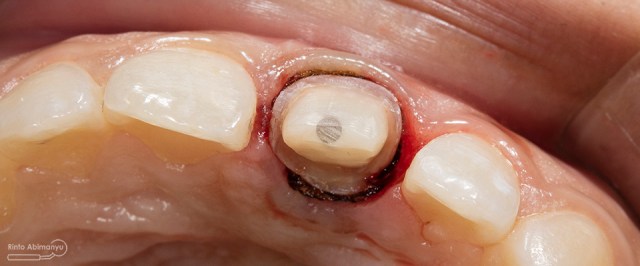

ini hasil preparasi gigi-giginya…

Hasil preparasi tampak depan

Hasil preparasi tampak oklusal

Kemudian preparasi pembuatan crown dimulai… Saya menggunakan bur silindris diameter kecil dengan ujung round sehingga untuk membentuk tepi preparasi menjadi chamfer akan lebih mudah… Selesai preparasi dilanjutkan dengan pemolesan hasil preparasi agar halus dan tidak mengganggu saat pencetakan.. Kemudian dipasangkan retraction cord nomer 00.